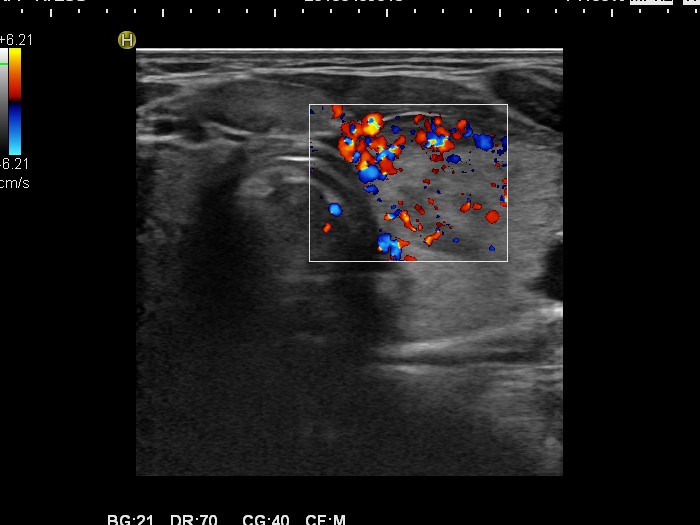

Graves' disease - Case 1049

Follow-up investigation 30 months after first visit (ultrasonographic picture 6)

Patient one year after discontinuation of thyrostatics in hyperthyroid state

Left lobe, transverse scan, color Doppler mode. The vascularization is increased.